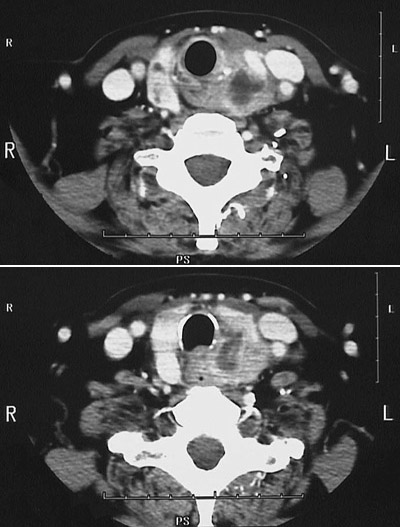

These serial views from a head CT scan demonstrates a mass with variable density in the left thyroid lobe. The mass impinges upon the trachea . The mass involved the recurrent laryngeal nerve, and produced the symptom of hoarseness.